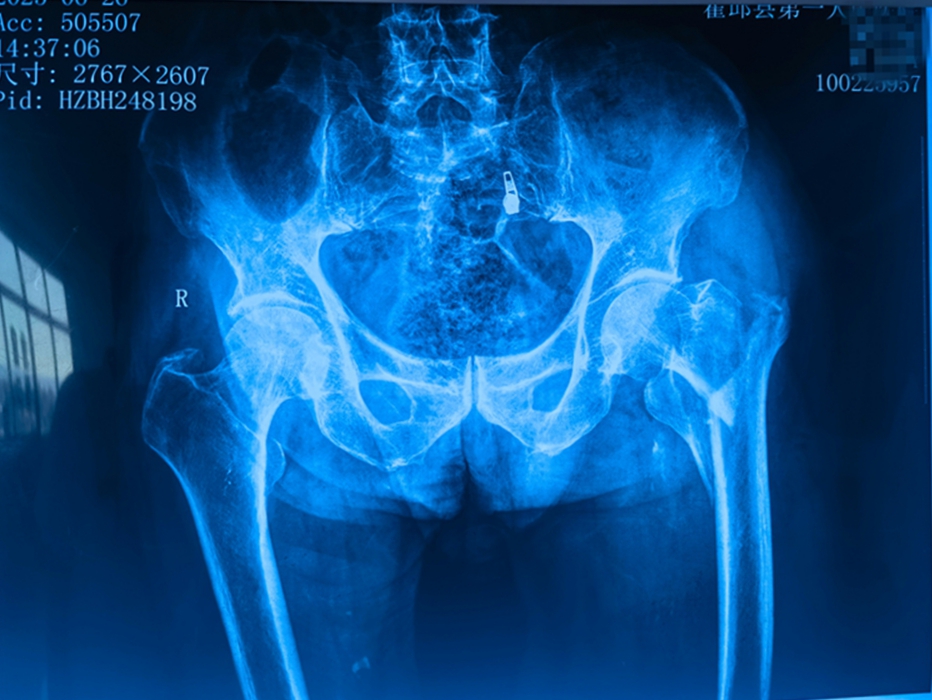

梁爷爷不慎摔倒致左股骨粗隆间骨折,术前更查出严重贫血和低蛋白血症。面对“人生最后一次骨折”的凶险与高龄挑战,骨科主任王家宁团队迎难而上。他们迅速联合输血科精准输血、输注白蛋白改善状态,筑牢手术安全基础。 同时,依托省级区域(专科)医疗中心平台,安医大二附院骨科许新忠教授亲临主刀,采用先进的“闭合复位髓内钉内固定术”(创伤小、出血少、恢复快)。团队精湛配合下,手术顺利完成。